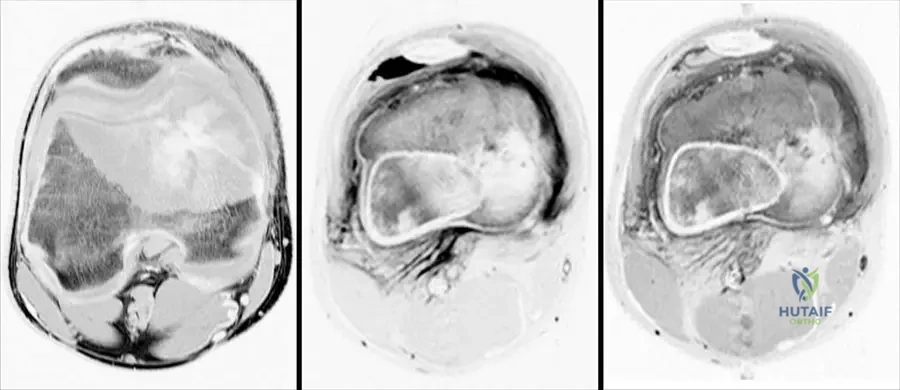

A 13-year-old male presents with a painful, rapidly growing mass in his distal femur. MRI images are obtained, as shown. These images demonstrate a large heterogeneous destructive mass in the bone with a large associated soft tissue mass. What is the most likely diagnosis based on these typical findings?

Rationale: The clinical context for Fig. 8.66 explicitly states these MRI images "show typical findings of an osteosarcoma. There is a large heterogeneous destructive mass in the bone with a large associated soft tissue mass." This is a classic presentation for osteosarcoma in this age group. Chondrosarcoma typically presents with chondroid matrix, Ewing sarcoma with a permeative pattern and onion-skin periosteal reaction, osteochondroma is a benign exostosis, and fibrous dysplasia is a benign fibrous lesion.

A 14-year-old male is diagnosed with a conventional osteosarcoma of the distal femur. Following initial radiographs and CT, the orthopedic oncologist orders an MRI of the entire femur. What is the MOST critical information this MRI is intended to provide?

Rationale: MRI is the most accurate imaging tool for determining the intraosseous and extraosseous extent of the tumor. It is also important to image the entire bone involved with osteosarcoma to evaluate for skip metastasis. This information is crucial for surgical planning and determining resection margins. Confirming osteoid matrix is done by biopsy. Assessing mineralization is better with CT. Pulmonary metastases are evaluated with chest CT. Differentiating benign from malignant is usually achieved with initial radiographs and biopsy. The image (Fig. 8.66 a–c) shows how MRI clearly delineates the extent of the mass.